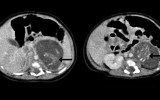

First thought to be a tumour, when doctors cut open the mass they found two tiny little humans complete with arms and legs, bones, brains, and underdeveloped organs.

If these were indeed the baby’s brothers and/or sisters, it would be an example of a very rare condition known as ‘foetus-in-fetu’, which has been reported only 200 times in medical literature, the report in the Hong Kong Medical Journal said.